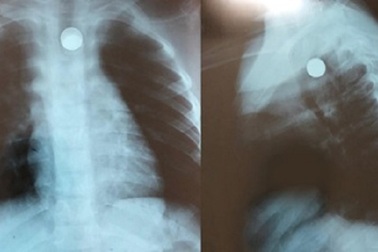

Bé trai gặp nạn khi ngậm viên bi sắt trong miệngĐang ngậm viên bi sắt trong miệng thì bị cha mẹ phát hiện bắt nhả ra nhưng cậu bé lại nuốt vào. Viên bi đã kẹt ở vùng thực quản khiến bệnh nhi không ăn uống được.